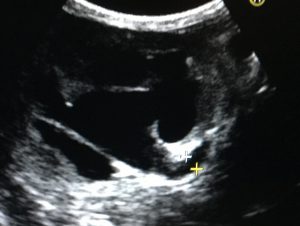

超音波検査で 消化管の表面は荒れていましたが、左腎盂、尿管拡張が認め その先には2.4mmほどの結石が存在しました。

矢印は左尿管です。通常は、確認できません。

矢印は尿管結石(白く細長い)です。途中で詰まっていました。